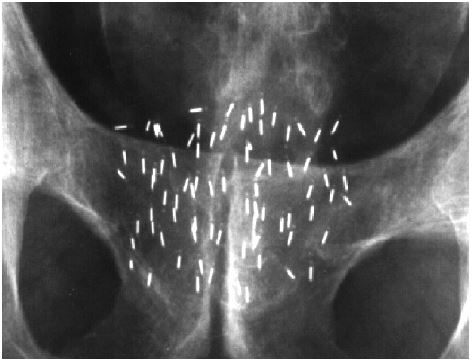

This procedure involves implanting radioactive Iodine-125 seeds directly into the prostate gland. The seeds continuously give off low level radiation for about one year. Each seed is 5mm in length and 0.5mm thick. The seeds are held together in a strand for implanting as can be seen here in the illustration.

The seeds are loaded into special needles. These are then implanted into your prostate gland through perineal area (the skin between your scrotum and anus).